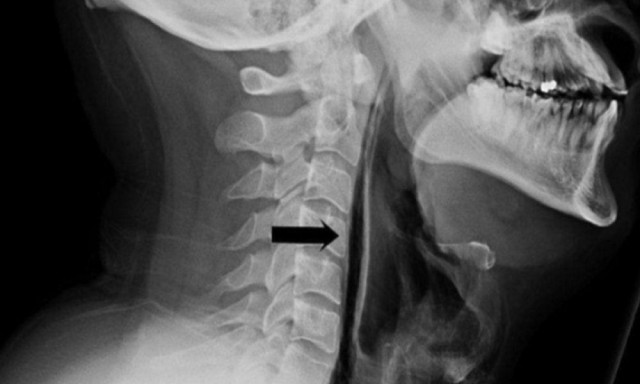

34-летний поступил в больницу после сильного чиха, который он пытался сдержать, рассказали в Суоярвской больницы

"С жалобами на острую боль при глотании и на изменения в голосе. Он попытался сдержать позыв чихнуть, зажав ноздри пальцами, но когда чихнул, то почувствовал толчки в шее и затем обнаружил, что шея опухла", — сообщили в больнице.

Пациенту сделали рентген, который указал на спонтанный разрыв пищевода. Он привел к чрезмерному скоплению воздуха в шее перед трахеей. Врачи предупредили, что идея зажимать рот и нос, чтобы не чихать, — опасна. Это может привести к скоплению лишнего воздуха в груди, разрыву барабанной перепонки и даже разрыву аневризмы головного мозга.

В Карелии мужчина разорвал глотку, пытаясь не чихнуть